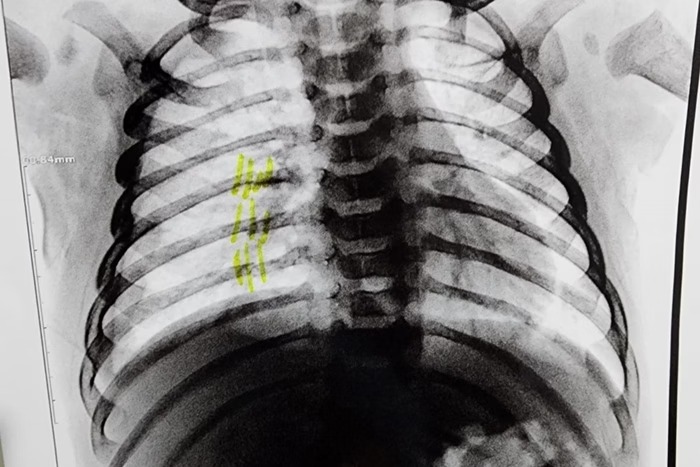

O delegado responsável pelo caso, Ruiter Martins, da Delegacia de Cabreúva, informou que os exames radiológicos confirmaram as fraturas, associadas a lesões externas, o que indicou espancamento.